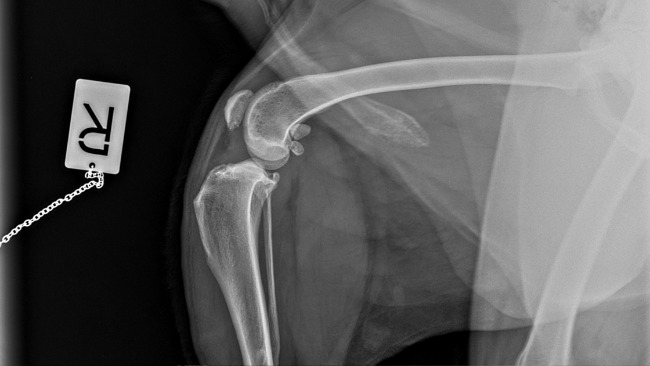

To tak dzielny, wspaniały, kochany zwierzak, że ciężko uwierzyć, że kilka dni temu przeszedł taką ciężką operację.

Nóżka Kokoszka, choć nadal obrzęknięta, dobrze się goi i nasz dzielny psiak stawia na niej swoje wielkie łapeczki.

Sam Kokosz jest teraz taki uśmiechnięty i pogodny, że wiemy, że decyzja o wykonaniu u niego pierwszej z trzech operacji łapek była słuszna i najlepsza.

Fot. Droga chłopaków do równowagi psychicznej. Wizyty w gabinecie lek.wet.